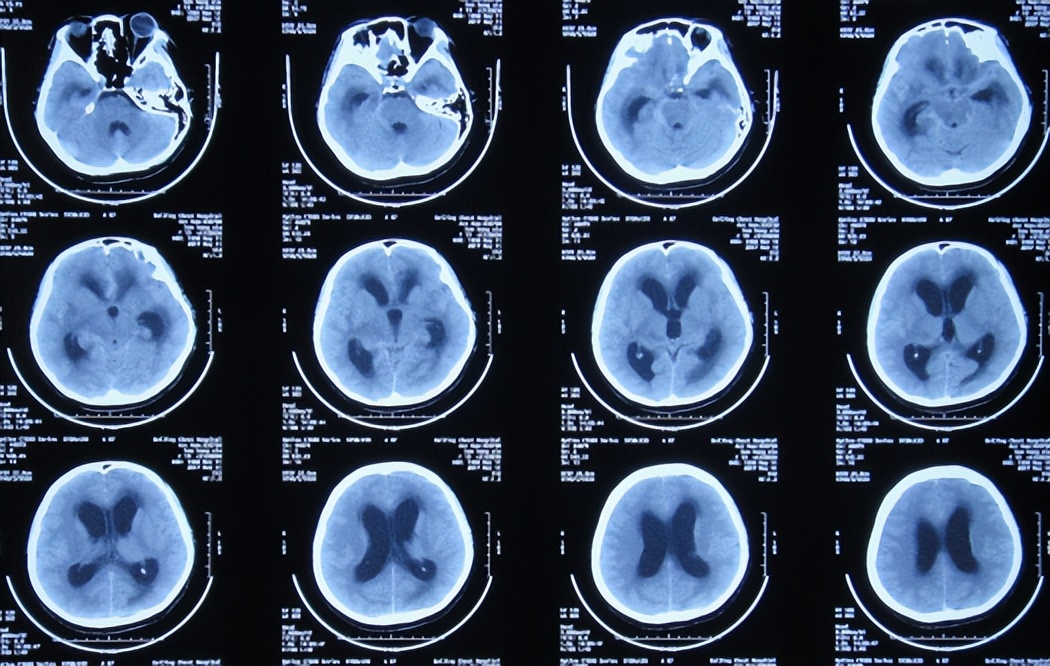

入院治疗3天后即2017年4月5日(发病后16天后),脑CT( 图-3 )后继续给予相关治疗。

图-3: 2017年4月5日脑CT

2017年5月11日(第4家医院入院治疗6天),颅压降至185mmH2O,体温变正常,但左眼睑下垂无改善,出现头痛,查头颅CT示脑室扩张( 图-7 );考虑结核脑膜炎性脑积水。

图-7: 2017年5月11日脑CT